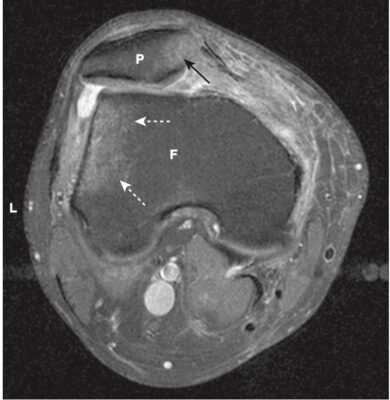

| Cơ xương | Đánh giá sụn chêm, gân, cơ Xương Viêm tủy xương Cột sống | Rách sụn chêm, tổn thương gân và dây chằng Đụng dập tủy xương; gãy xương ẩn hoặc do mỏi Giá trị tiên liệu âm tính cao nếu bình thường Bệnh lý đĩa đệm và thâm nhiễm tuỷ xương; phân biệt sẹo do phẫu thuật trước đó hoặc bệnh mới |